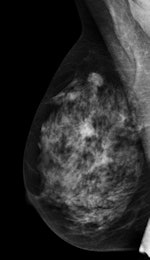

The Italian study was published online on 14 September in European Radiology. Lead author Dr. Gisella Gennaro, a medical physicist from the Veneto Institute of Oncology in Padua, and colleagues compared the clinical performance of standard two-view digital mammography with the combination of one-view tomosynthesis (mediolateral oblique) and one-view mammography (craniocaudal). A multiple-reader, multiple-case receiver operating characteristics (ROC) experiment was performed, and clinical performance was reported in terms of area under the ROC curve (AUC), sensitivity, and specificity.

Six breast radiologists reviewed images from 250 patients who underwent bilateral mammography and DBT imaging. Mammography and DBT images with the adjunct of the craniocaudal mammography view from 469 breasts were evaluated and rated independently by six readers.